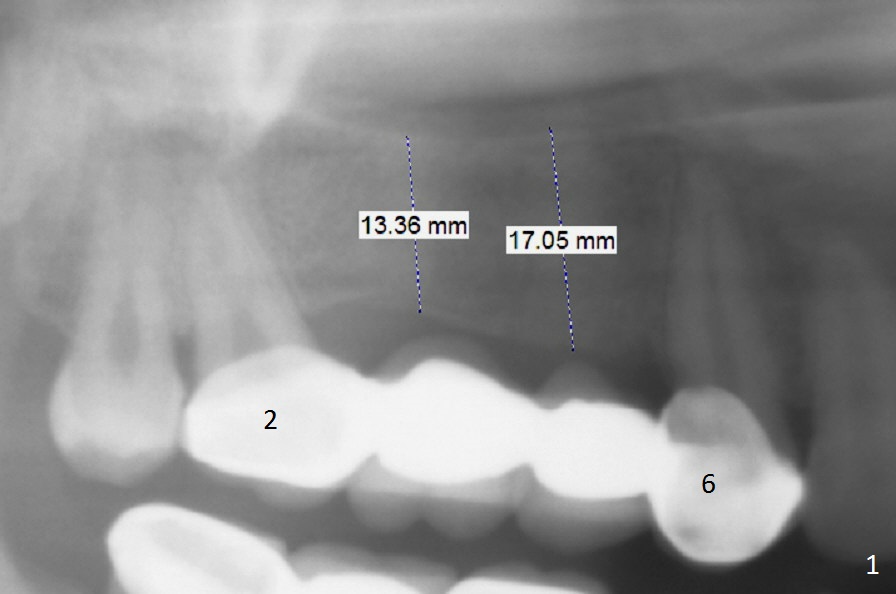

A 39-year-old woman has mobile FPDs at #2-6 (Fig.1,2) and 18-21 (Fig.3,4). Panoramic X-ray (Fig.1,3) was taken 10 years ago, while PAs (Fig.2,4) were taken lately. The abutment at #6 appears to be fractured (Fig.2 >), while that at #18 has 2nd caries (Fig.4 *). Removal of the FPDs determines salvageability of the abutments. The one at #6 may need RCT, B-U and crown or extraction/implant. In any event, implants will be placed at #3, 4, 18 and 20. To avoid the Inferior Alveolar Canal and Mental Loop, the implants will be as lingual as possible (Fig.3,4). For surgical and restorative stents, take Alginate impression as soon as the patient arrives.